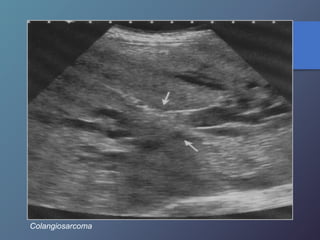

Colangiocarcinoma

Linfoma No H.

Colangiosarcoma

• 76.

• Se observauna infiltración parenquimatosa sutil. • Afecta la triadas portales. Colangiocarcinoma